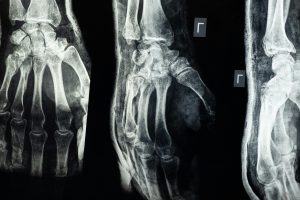

Cirugía mínimamente invasiva: Revolucionando el tratamiento del dolor musculoesquelético